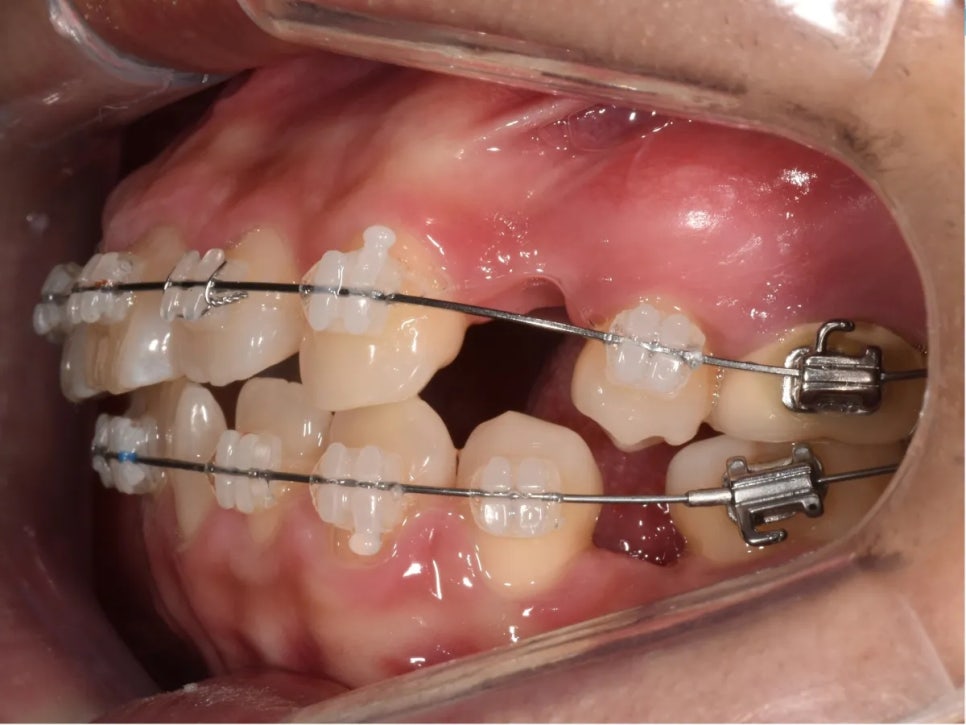

치료 과정 ① – 정출된 어금니 함입

교정 치료 초반, 가장 먼저 착수한 건 정출된 위 오른쪽 첫째 어금니를 제자리로 밀어넣는 작업이었습니다. 이 어금니가 내려와 있는 한 오른쪽 교합을 절대 정상으로 만들 수 없습니다.

미니스크류를 고정원으로 삼아, 정출된 어금니에 함입력(위로 밀어넣는 힘)을 가했습니다. 함입이란, 뼈 속으로 치아를 밀어넣는 이동을 말합니다. 사실 함입은 교정에서 가장 어려운 치아 이동 중 하나입니다. 미니스크류 같은 현대적인 도구가 없었다면 이 정도의 함입은 매우 힘들었을 것입니다.

이렇게 미니스크류에서 힘을 걸어 어금니를 뼈 속으로 밀어넣습니다

한편, 반대쪽(왼쪽 아래)도 작업이 필요했습니다. 두 번째 작은어금니가 빠진 자리 옆의 치아들이 빈 공간 쪽으로 상당히 쓰러져 있었기 때문입니다. 이 치아들을 똑바로 세우는 작업도 동시에 진행하였습니다.

치아가 빠진 부위의 인접 치아가 상당히 쓰러져 있어, 세워주는 작업이 필요했습니다.